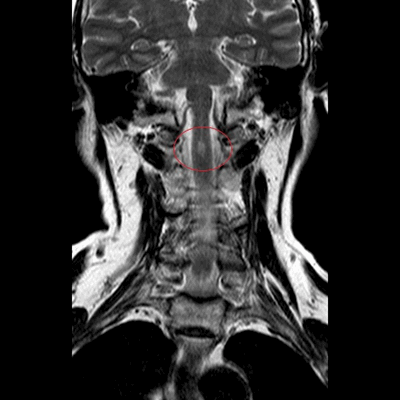

МРТ шеи: оценка сколиоза (коронарная плоскость, Т2 последовательность, STIR)

Боль в шее может быть вызвана проблемой в самом позвоночнике или в окружающих его мышцах. Наиболее часто дискомфорт в данной анатомической области обусловлен остеохондрозом, грыжей или протрузией межпозвонковых дисков, компрессией нервно-сосудистых пучков, иннервирующих спинной мозг, невралгией. Перед тем, как сделать выбор в пользу МРТ, врач оценивает характер боли и ее локализацию. Неприятные ощущения в области передней части шеи чаще свидетельствуют о заболевании трахеи, гортани, щитовидной железы, воспаленных лимфатических узлах, осложнениях со стороны уха. Для постановки диагноза в описанных ситуациях иногда достаточно проведения физикального и инструментального осмотра, ультразвуковой сонографии. Если пациент предъявляет жалобы на боль в задней поверхности шеи, усиливающуюся при повороте или наклоне головы, прострелы, ограничение в подвижности - для обнаружения проблемы обосновано сделать МРТ шейного отдела позвоночника. Магнитно-резонансное сканирование показывает структурные изменения в области интереса. Если боль носит функциональный характер, например, сопутствует миозиту, лучевая диагностика будет малоинформативна.